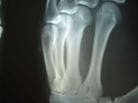

Published on 11/19/2004 		黑龙江双城市付丽被万家劳教所迫害得双手残疾(图)